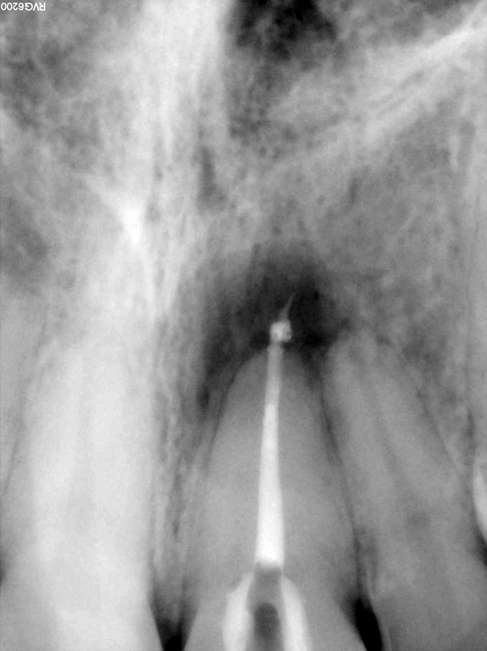

(9.) Preoperative radiograph of previously treated tooth No. 9, which received a diagnosis of acute apical abscess secondary to childhood trauma and recurrent endodontic pathology.

Figure 9

(10.) Posttreatment radiograph and cone-beam computed tomography (CBCT) scan following nonsurgical root canal re-treatment that resulted in incomplete resolution of symptoms in response to percussion and palpation.

Figure 10

(11.) Posttreatment radiograph and cone-beam computed tomography (CBCT) scan following nonsurgical root canal re-treatment that resulted in incomplete resolution of symptoms in response to percussion and palpation.

Figure 11

(12.) Postoperative radiograph after apical surgery was performed using MTA as an apical retrofilling material.

Figure 12

(13.) Normal healing was noted clinically and radiographically at the 6-month follow-up appointment.

Figure 13